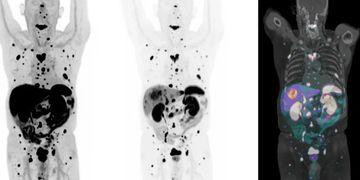

Molecular Imaging with Ultrafast Digital PET-CT and SPECT-CT

Our imaging capabilities combine the latest in PET-CT and SPECT-CT technology to deliver precise, reliable diagnostics.

PET-CT Imaging

PSMA PET-CT

Prostate cancer • Ga-68 PSMA (Illucix™) • F-18 PSMA (Pylarify™ or Posluma™)

PSMA PET targets prostate-specific membrane antigen, overexpressed by prostate cancer cells and metastases.

F-18 FDG

Oncology & beyond

FDG-PET uses a radioactive glucose analog to visualize metabolic activity. Primarily used in oncology (cancer imaging).

Precision Medicine at the Forefront

Florida Theranostics is built on the foundation of precision medicine, committed to delivering efficient, precise, and empathetic care to every patient.

We believe leveraging cutting-edge technology—including the United Imaging uMI Panorama PET/CT and the Veriton 400 SPECT-CT—brings us closer to that goal.